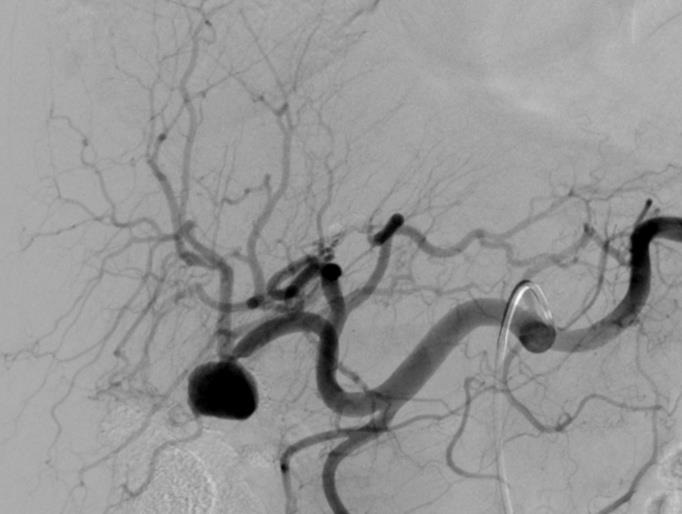

肺动静脉畸形

肺动静脉畸形分为单发、多发和弥漫性 |

这一例为多发性肺动静脉畸形 |

显示巨大静脉池显影 |

回流至肺静脉 |

肺动静脉畸形

选择其中一支畸形的滋养动脉 |

造影剂经静脉池回流至肺静脉 |

造影剂经静脉池回流至肺静脉 |